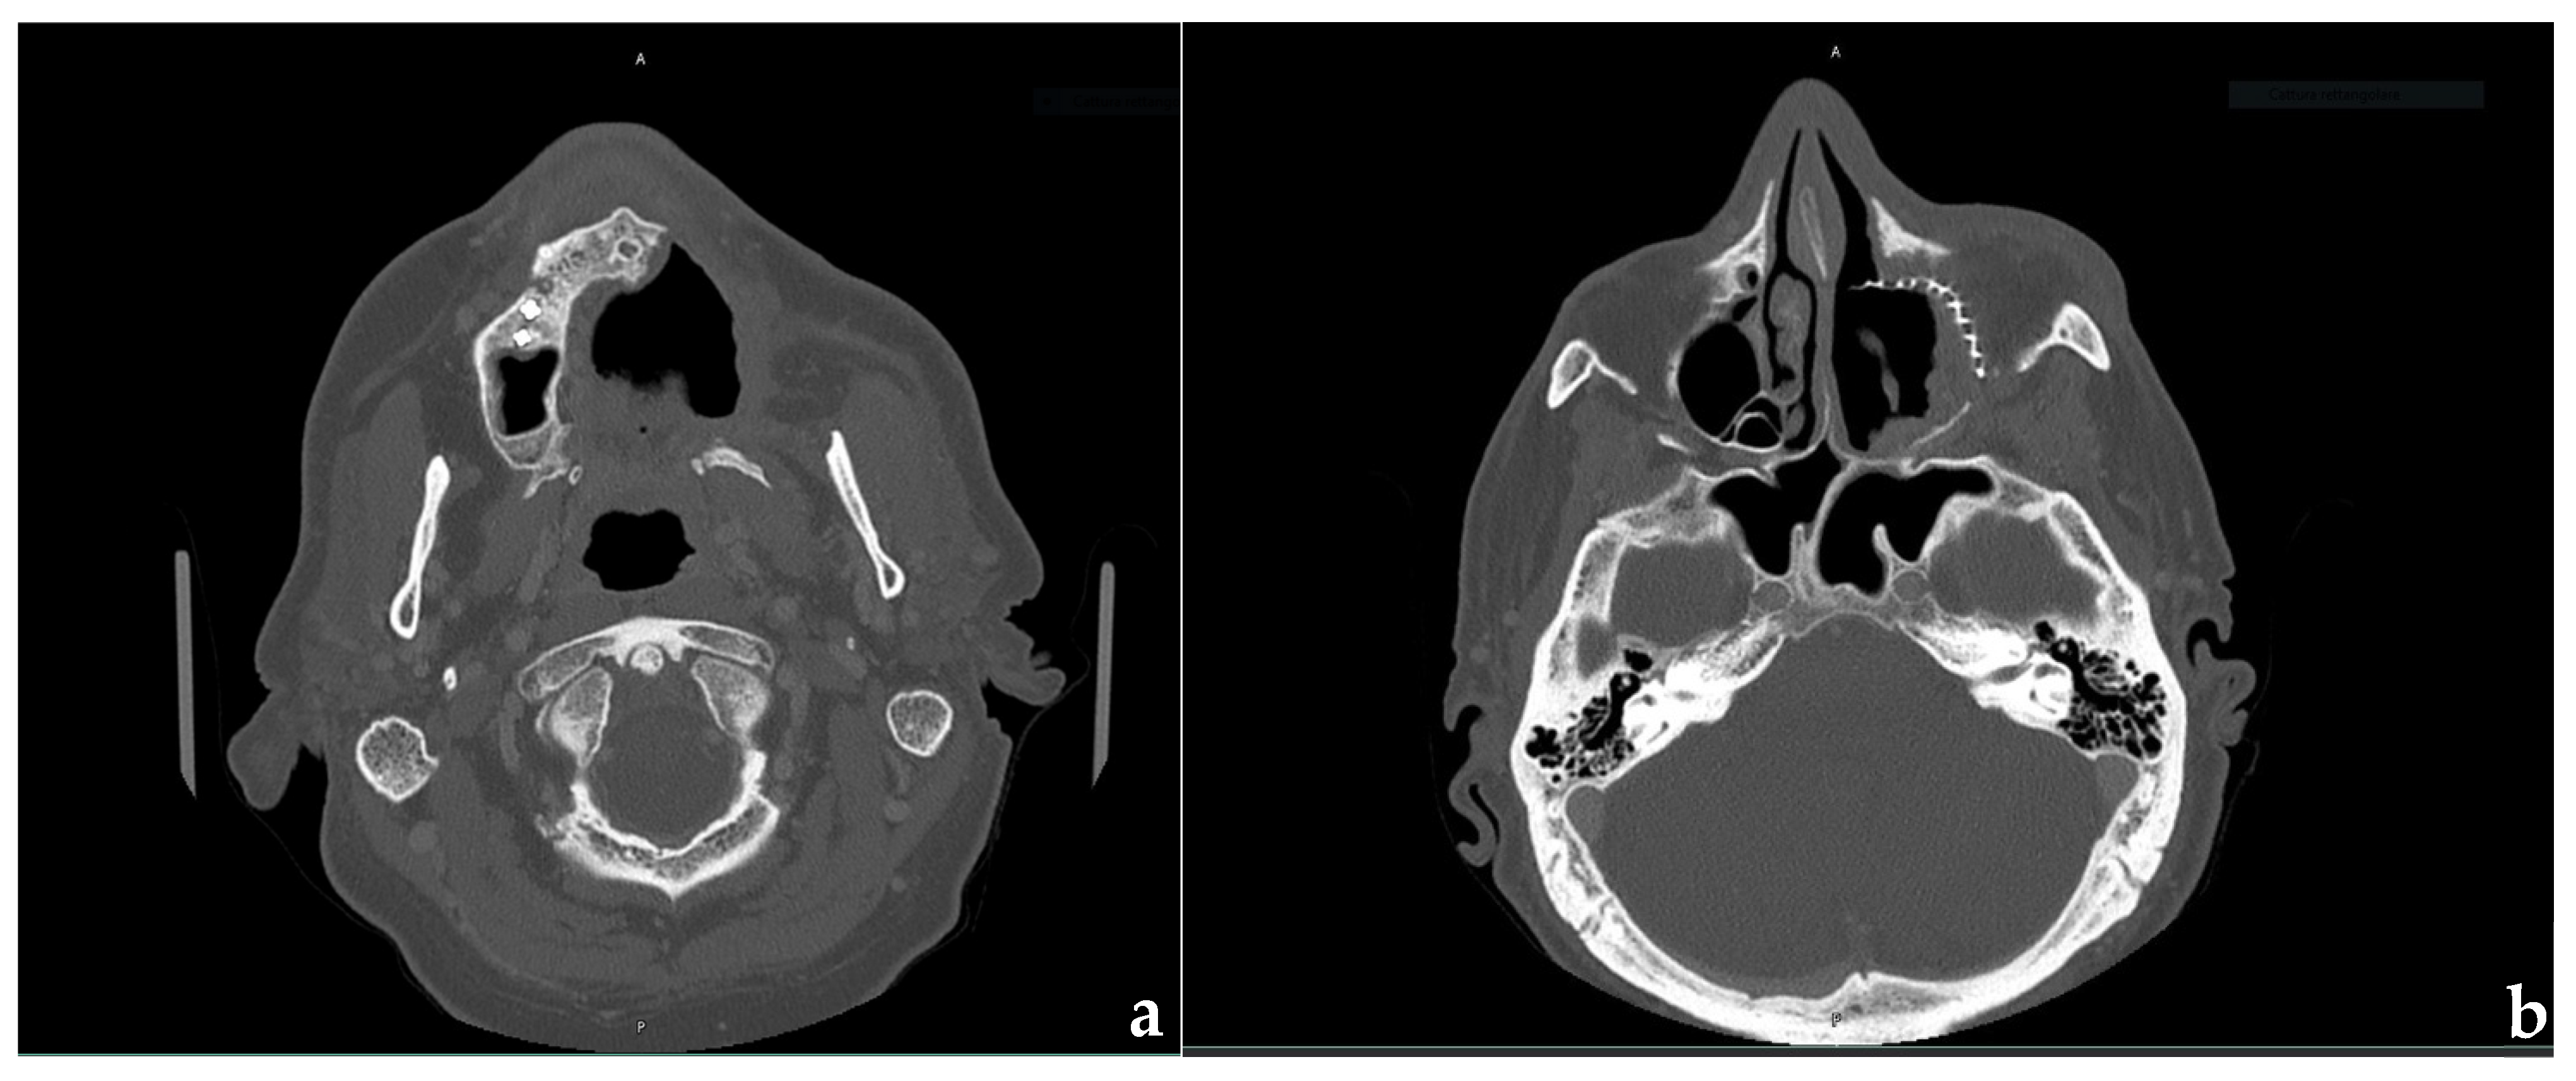

2. Clinical Case Presentation

2.1. Surgical Procedures